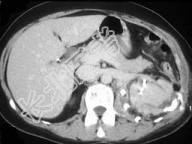

- 单项选择题如图所示,这两个时相提示 ( )

A、肾细胞癌

B、动静脉瘘

C、肾窦对比剂溢出

D、以上都有可能

E、以上都不是